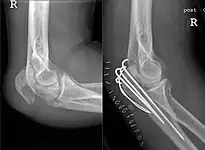

Tension band fixation

Tension band fixation is the most common form of internal fixation used for non-comminuted olecranon fractures.[5] It is typically reserved for noncomminuted fractures that are proximal to the coronoid.[2] This procedure is performed using Kirschner wire (K-wires) which converts tensile forces into compressive force.[2]

Intramedullary fixation and plates

Single intramedullary screws can be used to treat simple transverse or oblique fractures.[5] Plates can be used for all proximal ulna fracture types including Monteggia fractures, and comminuted fractures.[2]